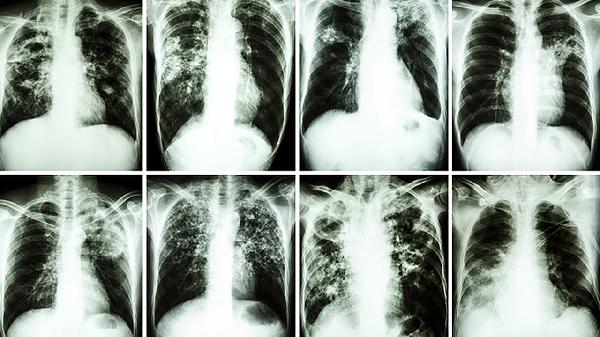

诊断重度肺阻塞性通气障碍需结合病史、体格检查及辅助检查。肺功能测试是主要手段,可评估气流受限程度。胸部X线或CT检查有助于排除其他肺部疾病,动脉血气分析可评估氧合状态。